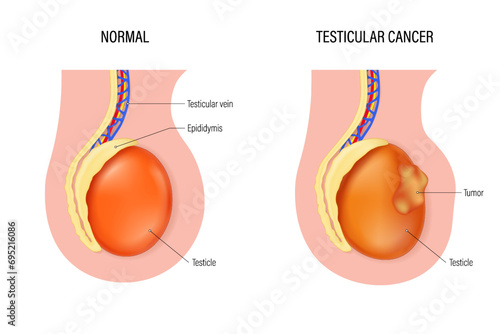

Testicular - Posters, Quadros em tela